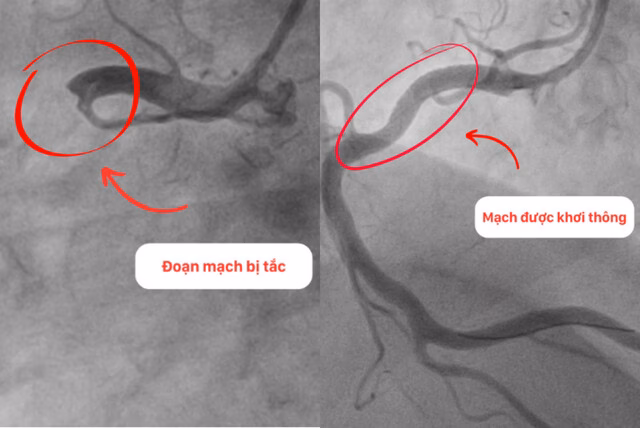

Chỉ hơn một giờ tính từ thời điểm nhập viện, thủ thuật chụp mạch vành qua da đã được thực hiện thành công. Kết quả chụp mạch cho thấy huyết khối gây tắc hoàn toàn ngay từ đoạn đầu động mạch vành phải, một trong ba động mạch quan trọng cấp máu nuôi quả tim của người bệnh. Với chiến lược khẩn trương và thao tác cẩn trọng, các bác sĩ đã hút thành công 4 cục huyết khối lớn ở đoạn đầu động mạch vành phải, nơi mạch xoắn vặn và rất khó thao tác.

Quá trình đặt stent đã diễn ra thành công nhờ sự phối hợp nhịp nhàng giữa hình ảnh siêu âm trong lòng mạch và hình ảnh chụp mạch qua da rõ nét của hệ thống máy móc hiện đại. Toàn bộ ê kíp can thiệp đã vỡ òa khi khơi thông dòng máu nuôi tim cho bệnh nhân. ThS.BS. Nguyễn Văn Hải, trưởng khoa Tim Mạch – Tim mạch can thiệp BVĐK Hồng Ngọc, trưởng kíp can thiệp cấp cứu cho bệnh nhân, cho biết rằng đây là trường hợp thứ 3 bị nhồi máu cơ tim do huyết khối tắc hoàn toàn đoạn gần của mạch vành mà họ can thiệp thành công trong vòng 1 tuần qua.